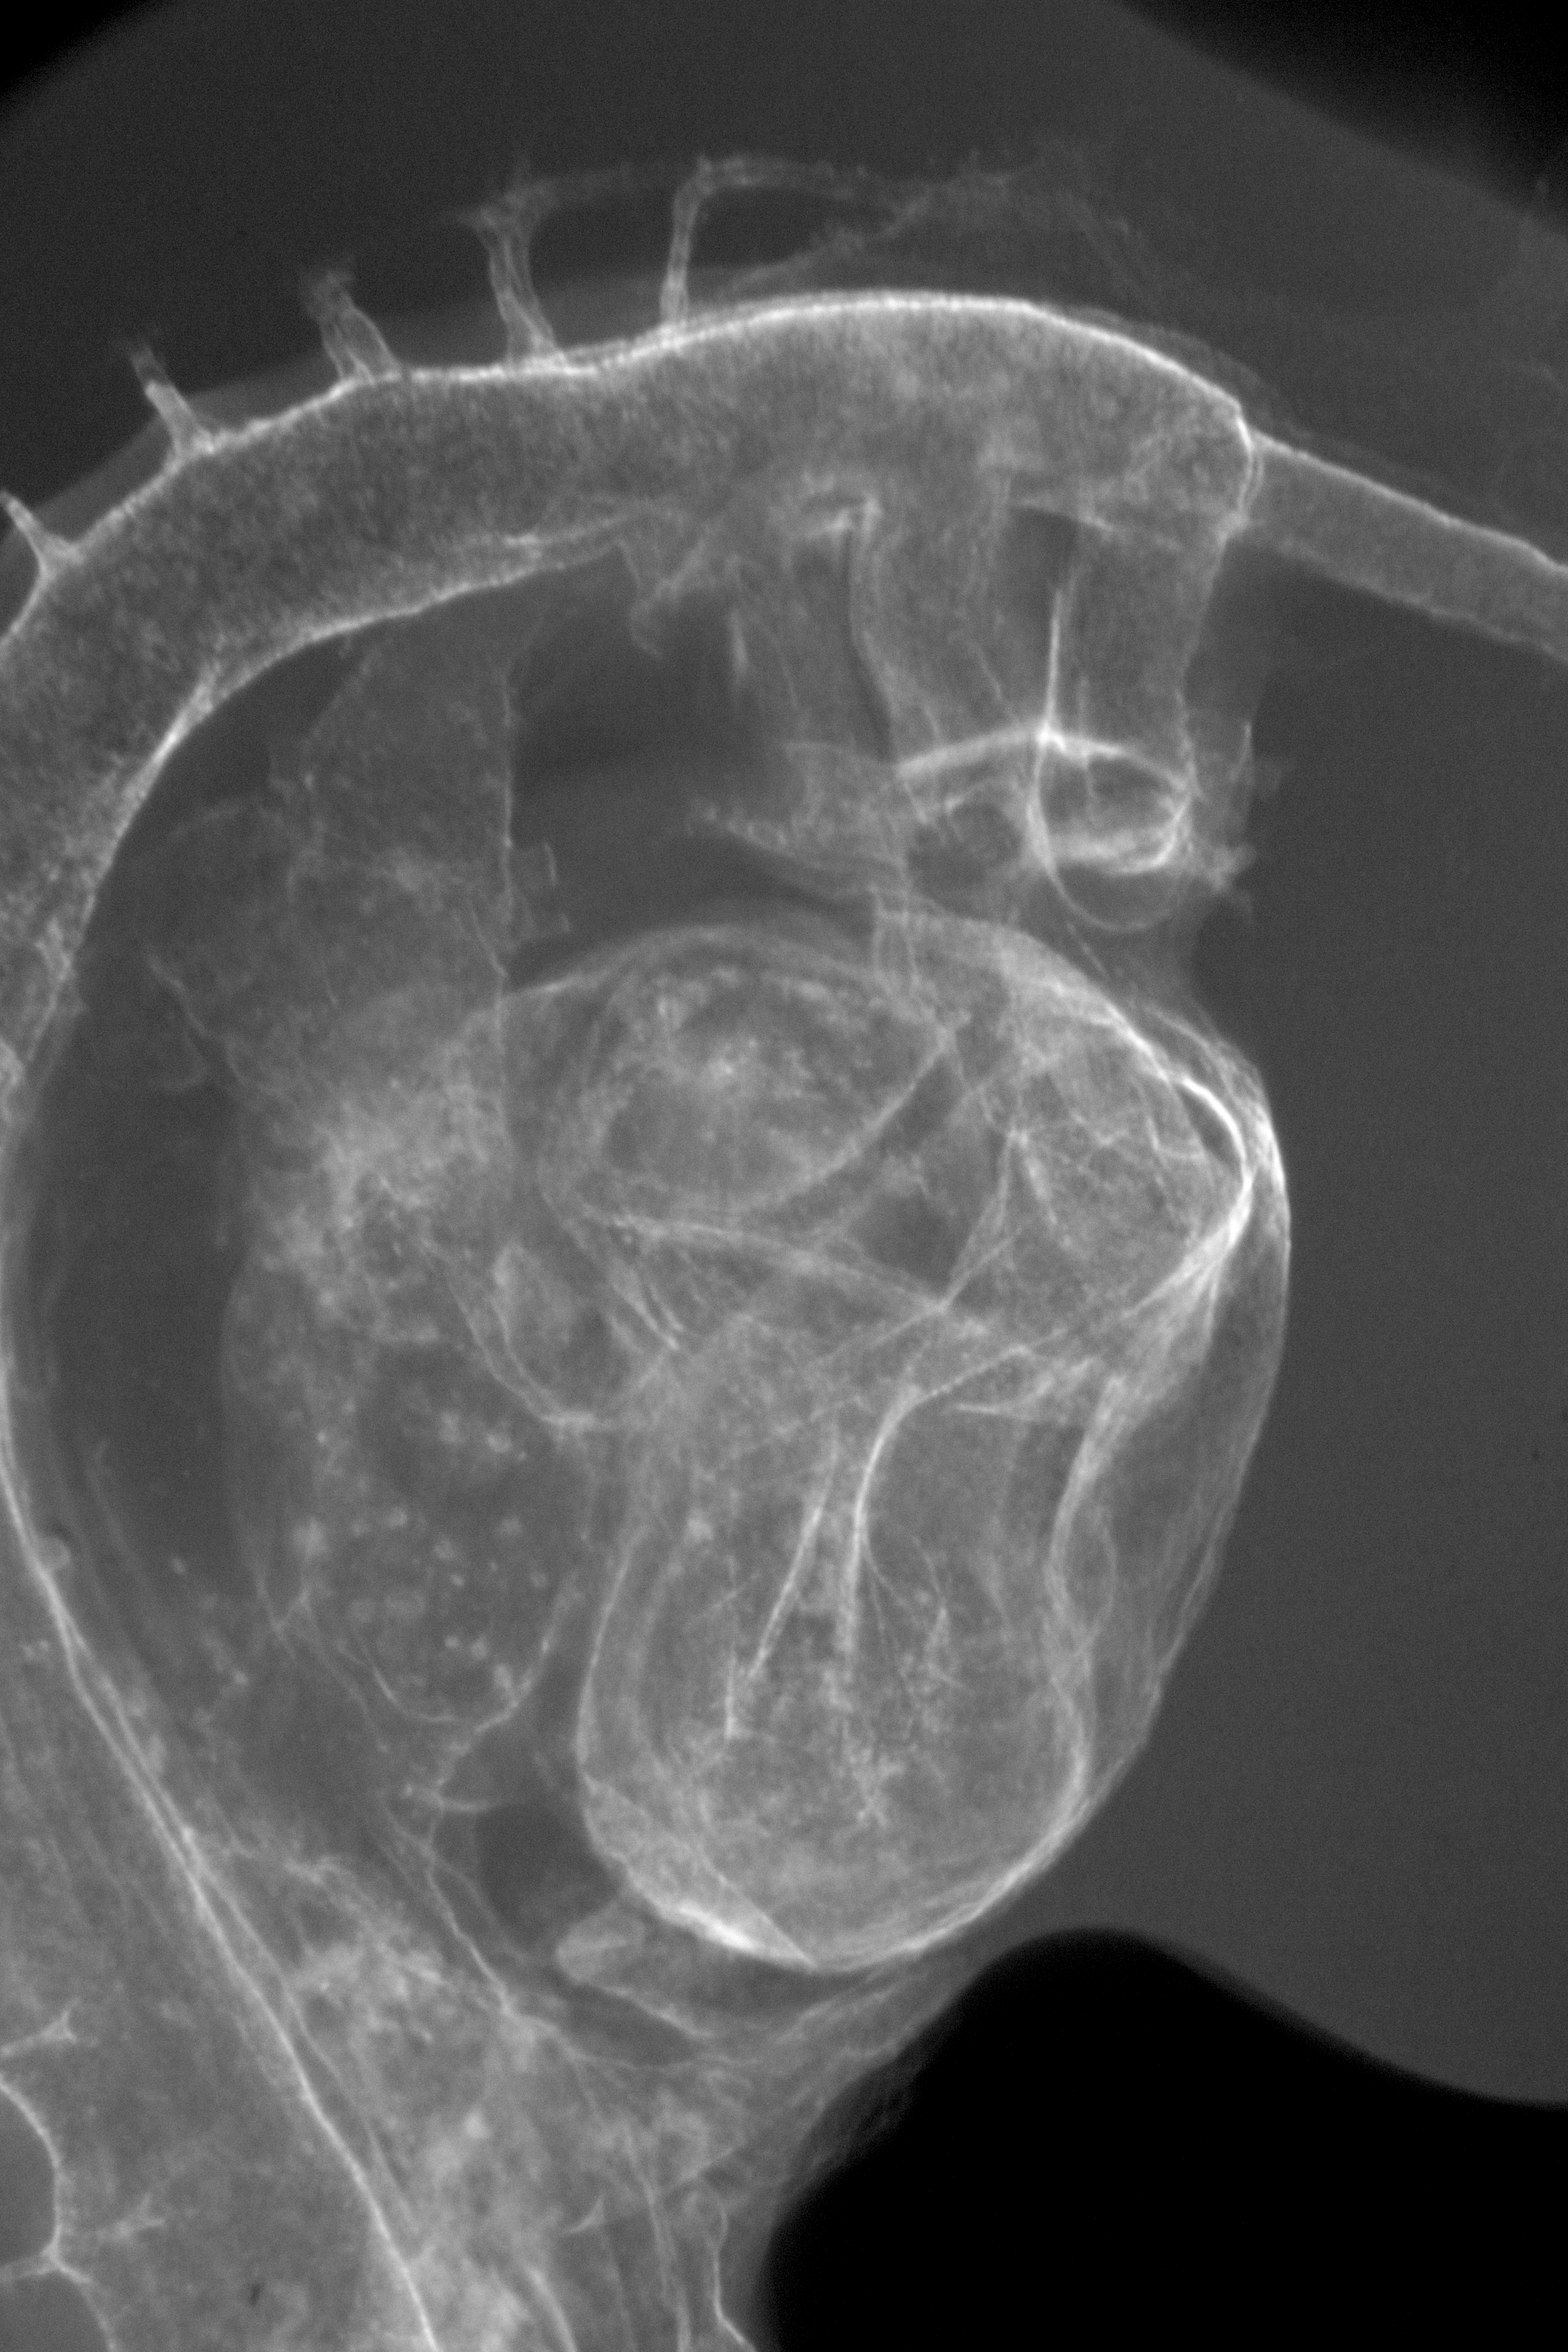

Chick Embryo Microangiography

Hamburger-Hamilton (HH) Stage 18 (approx. 3 days)

Drawing